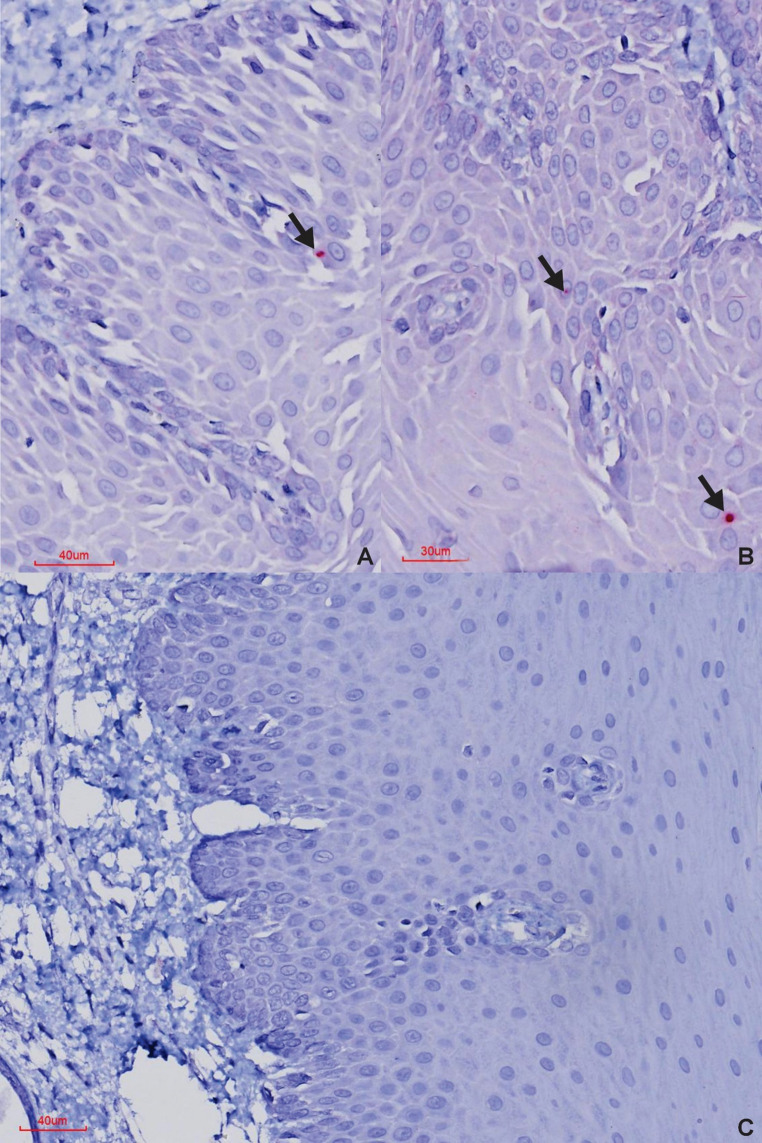

BaseScope™ in situ hybridisation (Advanced Cell Diagnostics, USA) was used to detect foot-and-mouth disease virus (FMDV), species Aphthovirus vesiculae, in formalin-fixed paraffin-embedded tissues from African buffalo (Syncerus caffer, n = 15) culled from the Kruger National Park - where the South African territories (SAT)-1, -2 and - 3 serotypes are endemic - as part of their population management program. Foot-and-mouth disease viral RNA was consistently detected in the palatine tonsils and lungs, demonstrating these as primary sites of viral persistence. Detection in the retropharyngeal lymph nodes and interdigital skin was less frequent, while oropharyngeal tissue showed rare positivity. Other sampled tissues - including the tip of the ear, eyelid, tongue, lip, and coronary band - proved suboptimal for identifying FMDV-positive buffalo or carriers. These findings highlight the value of BaseScope™ for detecting low viral loads of FMDV in persistently infected African buffalo, with a notable predilection for the palatine tonsils and lungs.

BaseScope™原位杂交技术(美国先进细胞诊断公司)用于检测从克鲁格国家公园(南非领土(SAT)-1、-2和- 3血清型流行的地方)采集的非洲水牛(Syncerus caffer, n = 15)的福尔马林固定石蜡包埋组织中发现的口蹄疫病毒(FMDV),即水疱型Aphthovirus vesiculae,作为其种群管理计划的一部分。在腭扁桃体和肺部持续检测到口蹄疫病毒RNA,表明这些是病毒持续存在的主要部位。在咽后淋巴结和指间皮肤的检测较少,而口咽组织显示罕见的阳性。其他取样组织——包括耳尖、眼睑、舌头、嘴唇和冠状动脉带——被证明不是确定口蹄疫阳性水牛或携带者的最佳方法。这些发现突出了BaseScope™在持续感染的非洲水牛中检测低病毒载量FMDV的价值,特别是对腭扁桃体和肺部的显著偏爱。